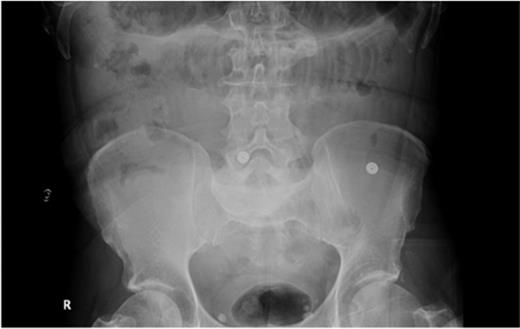

The second case described is of a 57-year-old gentleman who presented with a 3-day history of abdominal pain, vomiting and absolute constipation. His past medical history of note was a metallic aortic valve, although he was unable to give an accurate drug history on admission. On examination, his abdomen was distended with generalized abdominal tenderness and sluggish bowel sounds. Abdominal radiograph revealed dilated small-bowel loops (Fig. 3), and he was managed as a case of small-bowel obstruction, with intravenous fluid and a nasogastric tube.

Abdominal radiograph showing dilated small-bowel loops (Case 2).